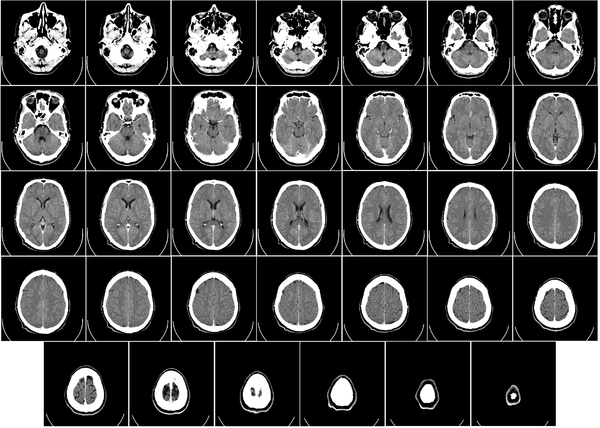

التصوير المَقْطَعي الحاسوبيX-ray computed tomography نظام تصوير بالأشعة السينية، يُسْتخدم لتصوير مختلف أجزاء الجسم مثل الرأس والقلب والبطن. ويستعين الأطباء بالتصوير المقطعي الحاسوبي على تشخيص الأمراض وعلاجها. وتسمى هذه التقنية أيضًا التصوير المقطعي المحوسب أو التصوير المقطعي المحوري المحوسب.

وللحصول على صورة أشعة مقطعية، يرقد المريض على طاولة تمر من خلال آلة فحص دائرية، تسمى المِسْند. وتوضع الطاولة بحيث يكون العضو المراد فحصه واقعًا عند منتصف المسند. وعن طريق أنبوب على المسند، تخرج أشعة سينية مخترقةً جسد المريض، ثم تدخل إلى مكشافات خاصة تقوم بتحليل الصورة التي ظهرت. ويدور المسند حول المريض للحصول على كثير من الصور من زوايا مختلفة. وبعد ذلك، يعالج الحاسوب المعلومات الآتية من المكشافات، لينتج صورة مقطعية مستعرضة على شاشة فيديو. وعن طريق تحريك الطاولة داخل المسْند، يمكن للأطباء الحصول على العديد من الفحوص للعضو نفسه، أو للجسد كله.

تعود تسميتها إلى كون هذه الطريقة تعطى صورًا شعاعية على شكل مقاطع للجسم، يجري التصوير المقطعي المحوسب بواسطة جهاز خاص، يسمى جهاز التصوير المقطعي المحوسب أو الماسحة المقطعية المحوسبة، تتميز هذه الطريقة بدقتها، تعطي صورًا واضحة، ويمكن أن تعطي صورًا لأماكن قد تكون من الصعب تصويرها بالتصوير الشعاعي التقليدي، كذلك يمكن عملها بشكل سريع ودقيق.

يمكن للأطباء أن ينظروا داخل جسم المريض عن طريق طلب إجراء مسح للعظام والأوعية الدموية والأدمغة والأنسجة الرخوة بفضل ماسح التصوير المقطعي الحاسوبي (CT). بعد إجراء أول فحص طبي بالأشعة المقطعية للمريض في عام 1971، استخدم أطباء الأشعة عمليات المسح لتشخيص الأورام والصدمات والتخطيط للعلاج الطبي والجراحي والإشعاعي في جميع أجزاء جسم الإنسان تقريباً.

داخل الجهاز على شكل كعكة الدونات، حيث يستلقي المرضى على الطاولة بينما يتحرك ببطء عبر الماسح الضوئي، تدور الآلة حولها. أثناء دورانه، يرسل شعاعاً رفيعاً من الأشعة السينية عبر الجسم، والذي يتم جمعه على الجانب الآخر من الجهاز ونقله إلى برنامج حاسوب، حيث يتم تحميله على شاشة لعرضها على تقنيي التصوير المقطعي المحوسب.

يتحول إلى صورة مقطعية أو مسح ضوئي أو "شريحة" لجسم الإنسان، ويستغرق في بعض الجلسات أقل من 15 دقيقة لإكمال الفحص بالأشعة المقطعية. لقد أصبحت ممارسة طبية موثوقة وروتينية على مر السنين. من عام 1996 إلى عام 2010، تضاعفت معدلات التصوير المقطعي المحوسب ثلاث مرات، مما أدى إلى إضافة ما يصل إلى 149 فحصاً لكل 1000 مريض يدخلون المستشفى.[2]